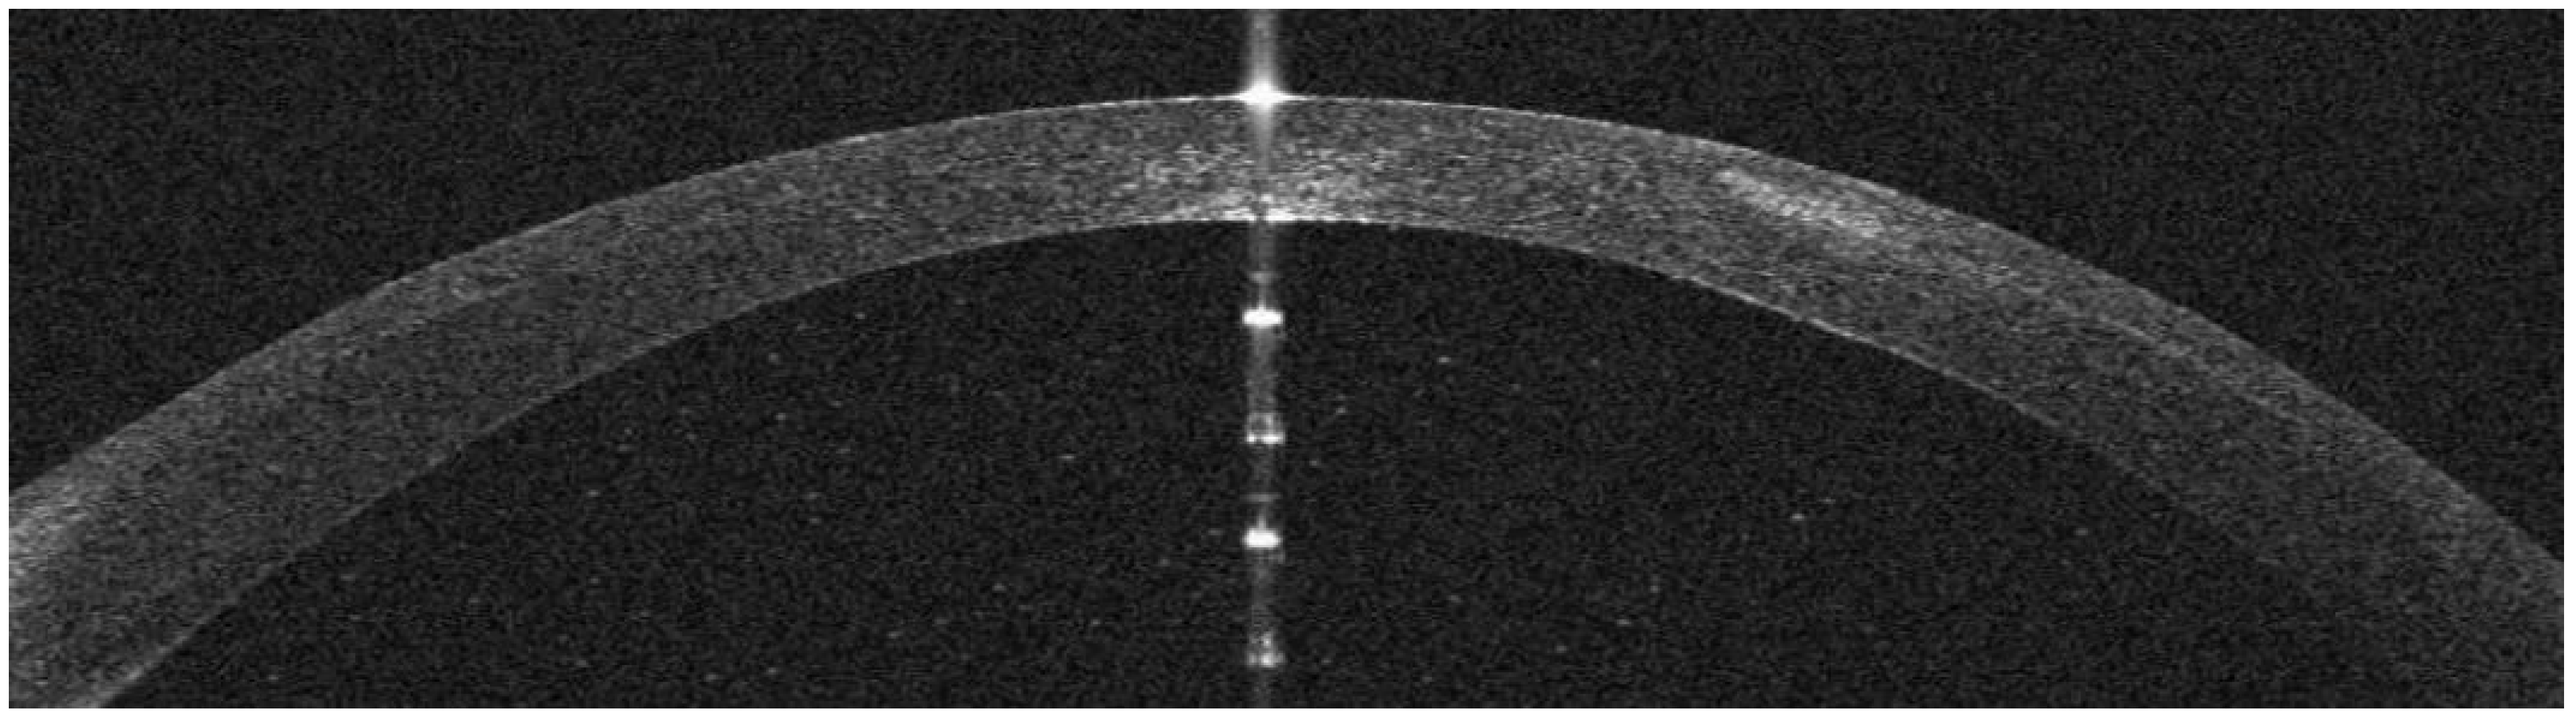

AS-OCT Features